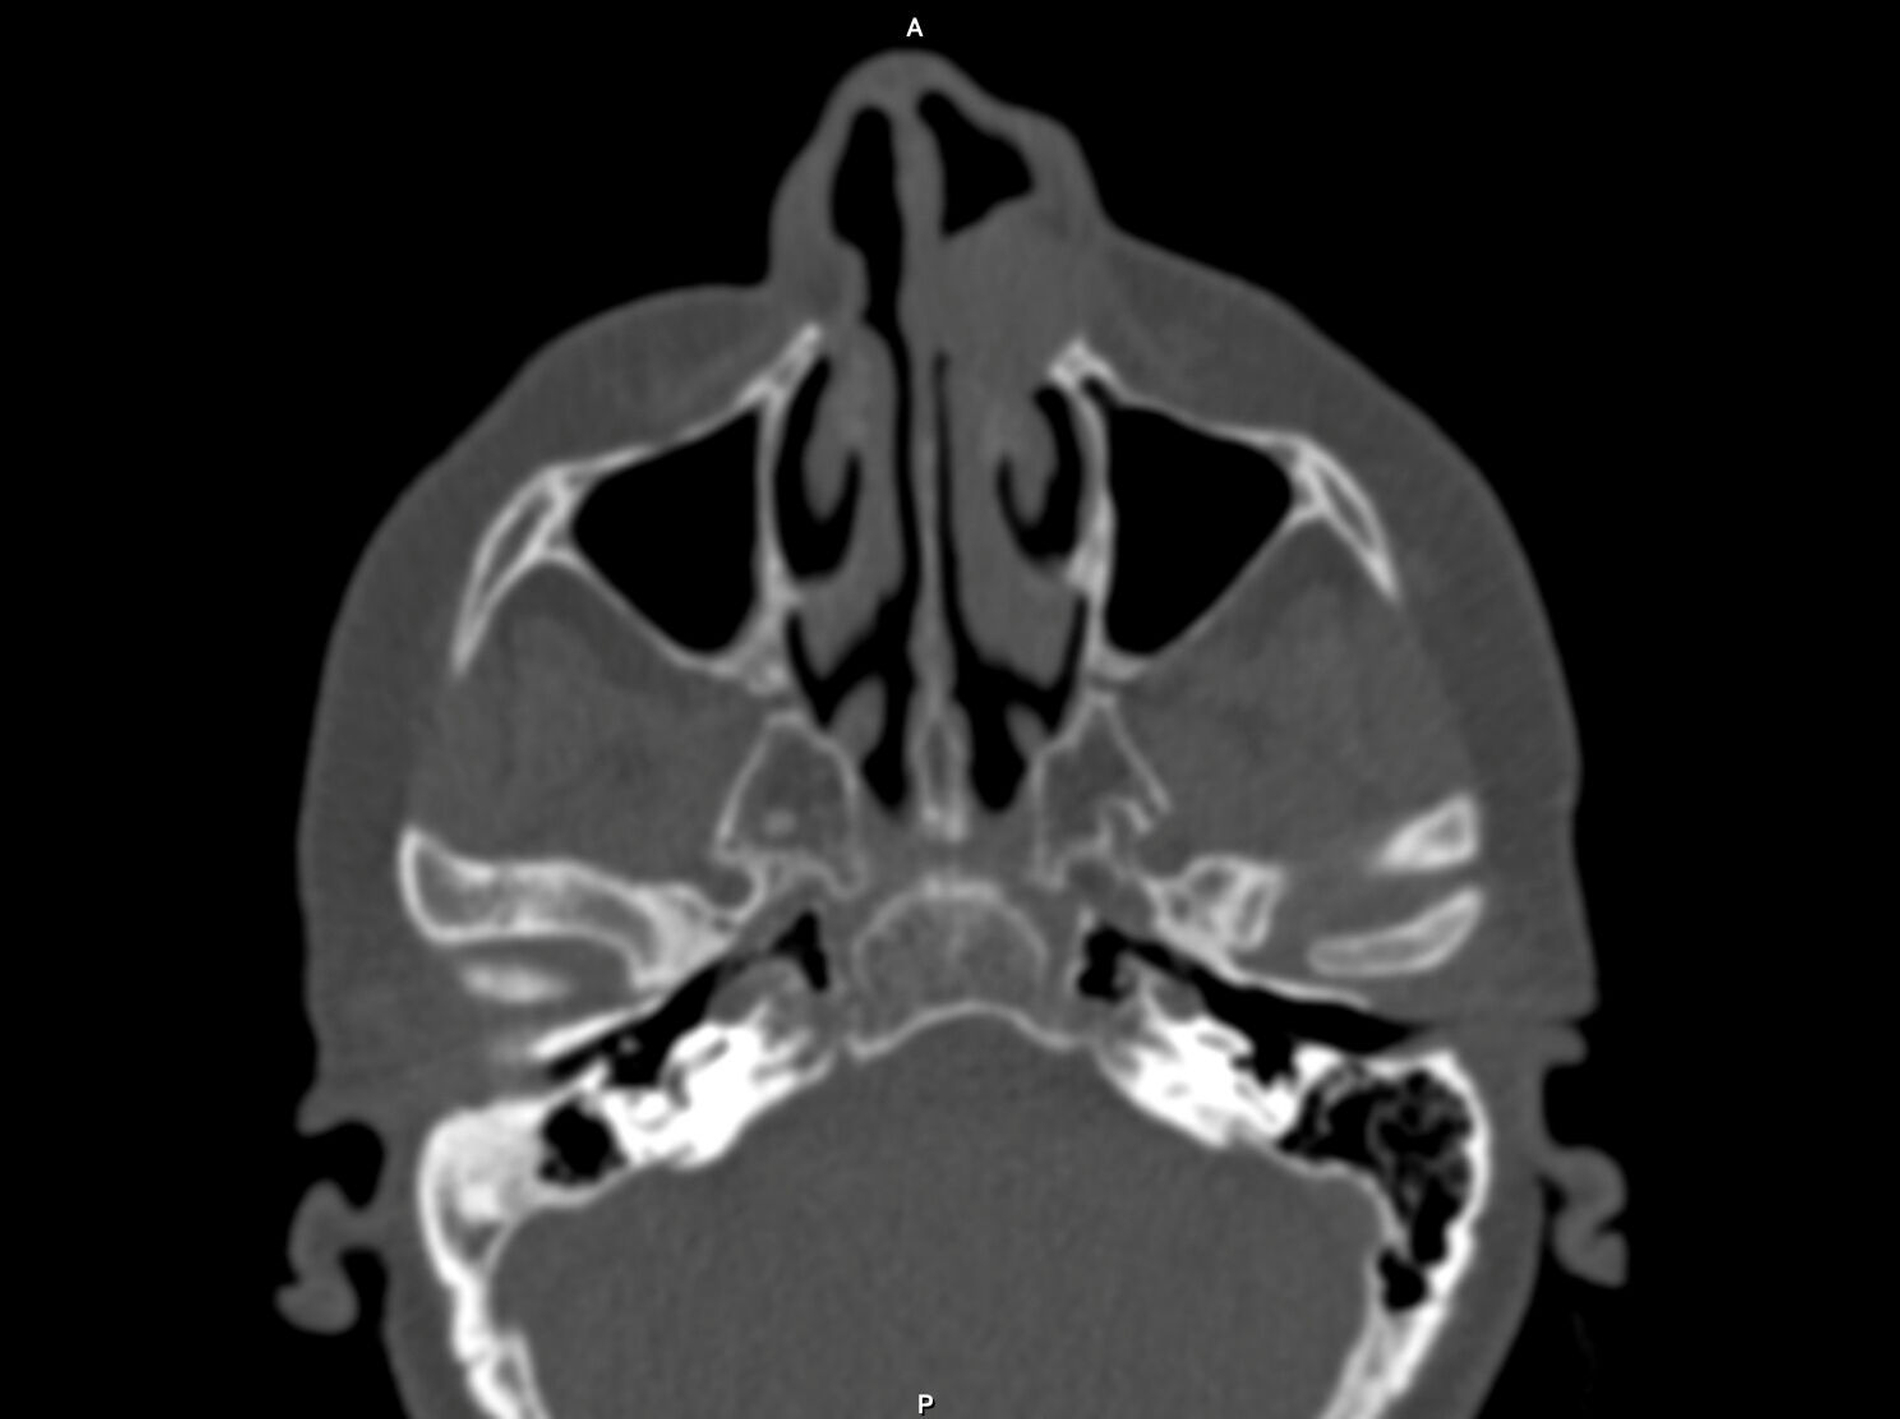

Nach Anfertigung einer Panoramaschichtaufnahme bestand der Verdacht auf das Vorliegen einer Zyste. Zur genaueren dreidimensionalen Diagnostik wurde eine native Computertomografie veranlasst. Im Übergangsbereich des linken Nasenvorhofs zur Nasenhaupthöhle imponierte eine runde, homogene Verschattung, die die Apertura pririformis im dorsalen Anteil erodierte und den Alveolarfortsatz nach palatinal bis zu den Wurzelspitzen der Zähne 21 bis 24 verdrängte (Abbildung 1). Daraufhin wurde die Indikation zur Zystektomie gestellt.